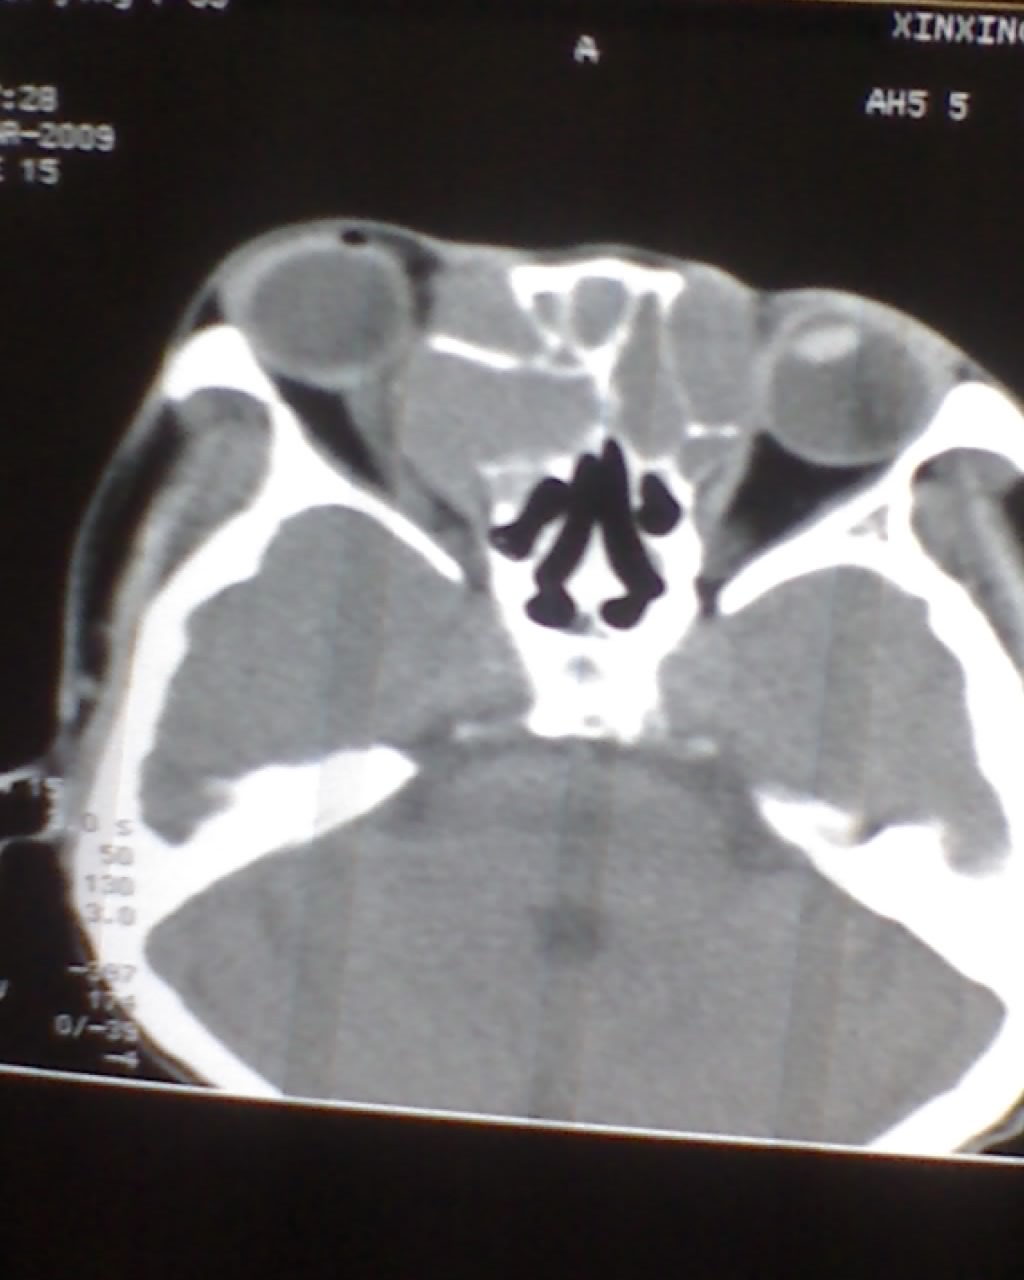

女,45岁,右眼突出,视力模糊来诊。

双侧筛窦可见软组织影充填,筛板破坏,肿块突向双侧眼眶内,以右侧为明显,右侧眼球向前外推压,右视神经稍外移。

考虑良性病变,内翻乳头状瘤可能性大,不除外息肉等。

考虑良性病变,内翻乳头状瘤可能性大,不除外息肉等。支持!(病灶明显起源于鼻窦,呈膨胀性生长,周边骨质吸收 破坏)。

双侧额窦,筛窦可见软组织影充填,筛板破坏,肿块突向双侧眼眶内,以右侧为明显,右侧眼球向前外推压,右视神经稍外移。

考虑良性病变,黏液囊肿可能性大,不除外内翻乳头状瘤等,建议强化.前者不增强.